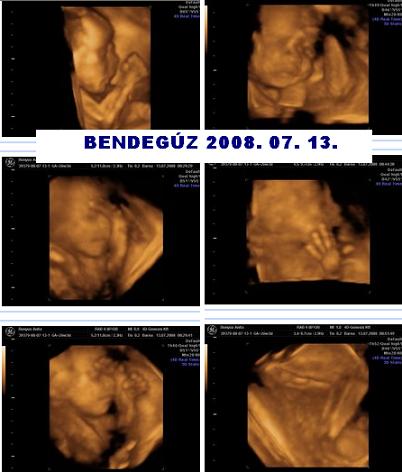

Nem tudtam nagyon visszaolvasni, de látok sok szép új képet! Klasszak nagyon. Felteszek én is egy összeállítást Kisfiúnkról, Bendegúzunkról. :) Kép

Zsemlyécske: Bendegúz nagyon édes :) Hogy álltok a házfelújítással?

Nagyon szuper volt, bár az arcát csak az utolsó 5 percben láthattuk, mert addig befordult, és a kezével is takart! Csilla fantasztikus volt, mindent megtett, hogy láthassunk mindenét, kaptam kávét, csokit, kis ugrálást, sétát, mindent, majd egy óra elteltével a kisasszony kegyeskedett felénk fordulni, és megmutatni durcás pofiját! Zabálnivaló volt!!!!!!

Teszek fel képet ha sikerül!